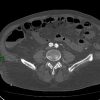

Nhồi máu ruột

» Thông tin: Nam giới – 85 tuổi.

» Lâm sàng: Đau bụng cấp.

# Dày thành ruột – Khí thành ruột – Khí tĩnh mạch mạc treo.